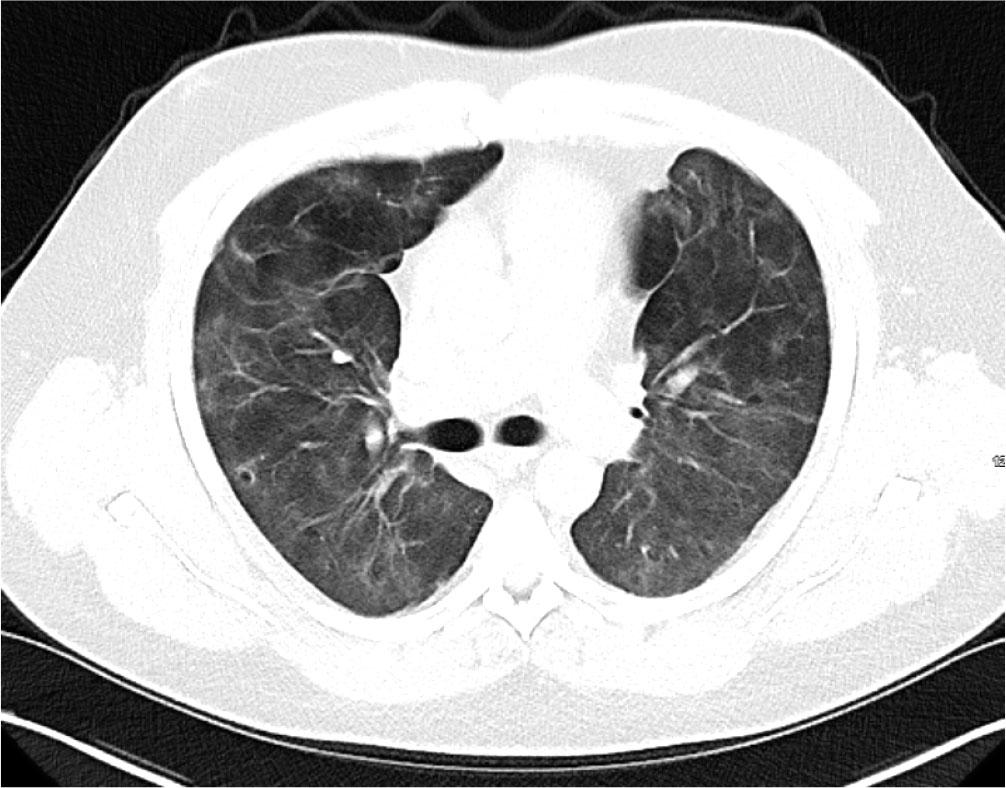

Initial blood tests on transfer demonstrated raised inflammatory markers; CRP 193, White cell count of 20.3 with a predominant neutrophilia. Haemoglobin12.0g/L, platelet count 496×109/L, creatinine 100umol/L, total protein 65g/L. ALT 112 IU/L, ALP IU/L, GGT 226 U/L, albumin 28g/L, total bilirubin 7umol/L. CK was unremarkable at 252 (ref range 44–272). A computed tomography (CT) thorax on transfer to our facility showed extensive bilateral consolidation and surrounding nodular ground glass opacification, in keeping with multi-lobar pneumonia (Figure 1). A bedside echocardiogram was essentially normal. Extensive microbiological investigations including sputum, blood, urine and broncho-alveolar lavage (BAL) culture for bacteria, mycobacteria and fungi, respiratory viral PCR from throat swab and BAL, legionella and pneumococcal urinary antigen yielded no positive results. There was no history of exposure to licensed medications or illicit drugs or factors known to cause lung disease. The presentation was one of severe Type 1 respiratory failure but notably there was no evidence of multi-system organ failure or hemodynamic compromise and hence was an unusual presentation for the initial working diagnosis of CAP with ARDS.

CT Thorax on Day 2 of admission showing extensive bilateral consolidation and surrounding nodular ground glass opacification, in keeping with multi-lobar pneumonia